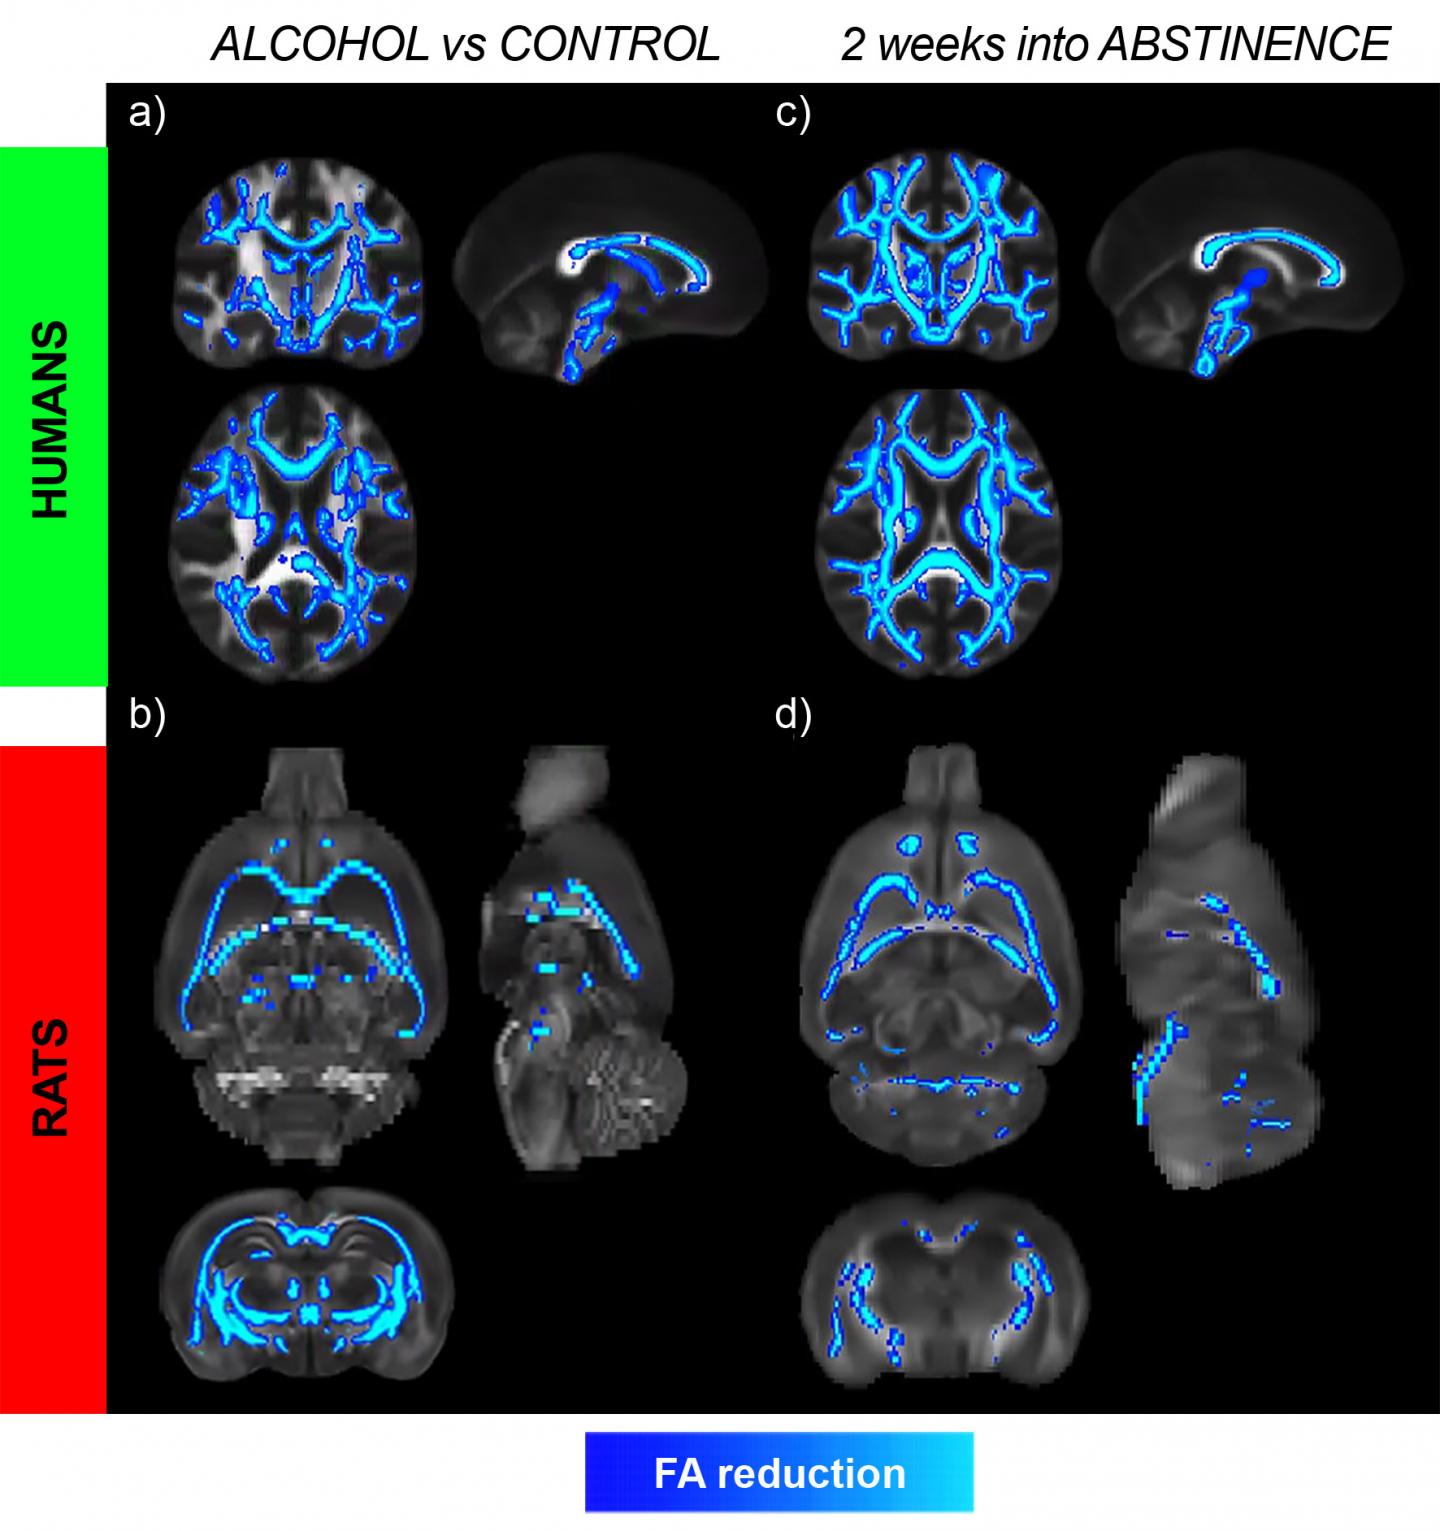

Now, a joint work of the Institute of Neuroscience CSIC-UMH, in Alicante, and the Central Institute of Mental Health of Mannheim, in Germany, has detected, by means of magnetic resonance, how the damage in the brain continues during the first weeks of abstinence, although the consumption of alcohol ceases.

The research, published today in JAMA Psychiatry , whose first author is Silvia de Santis, shows that six weeks after stopping drinking there are still changes in the white matter of the brain, as revealed by the neuroimaging study carried out on ninety voluntary patients interned for his rehabilitation treatment in a German hospital.

Another differential characteristic of this study is that it has been carried out in parallel in a model with Marchigian Sardinian rats with preference for alcohol, which allows to monitor the transition from normal to alcohol dependence in the brain, a process that is not possible to see in humans", explains Dr. De Santis.

The damages observed during the period of abstinence affect mainly the right hemisphere and the frontal area of the brain and reject the conventional idea that the microstructural alterations begin to revert to normal values immediately after abandoning the consumption of alcohol.

With the consumption of alcohol "there is a generalized change in the white matter, that is, in the set of fibers that communicate different parts of the brain. The alterations are more intense in the corpus callosum and the fimbria. The corpus callosum is related to the communication between both hemispheres. The fimbria contains the nerve fibers that communicate the hippocampus, a fundamental structure for the formation of memories, the nucleus accumbens and the prefrontal cortex, "explains Dr. Canals. The nucleus accumbens is part of the reward system of the brain and the prefrontal cortex is fundamental in decision making.